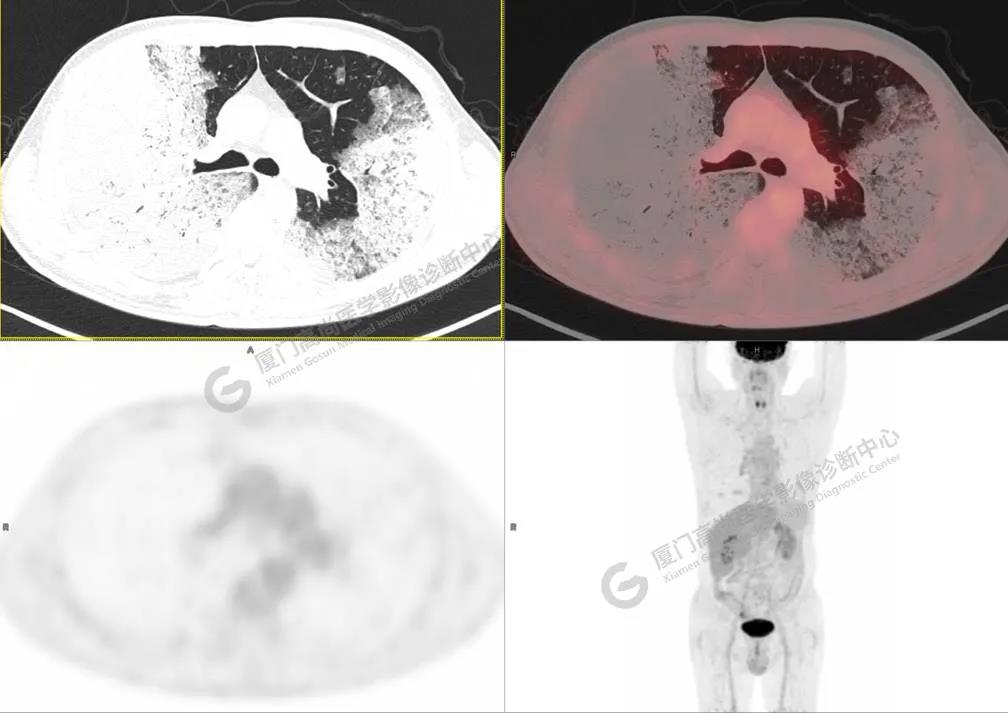

PET/CT影像圖

圖2

PET/CT所見(jiàn):雙肺大片實(shí)變影及磨玻璃影,部分呈地圖樣改變,累及右肺尖,部分放射性攝取輕微增高,SUVmax 1.77,其內(nèi)見(jiàn)多發(fā)支氣管充氣征象。

影像診斷: 雙肺大片實(shí)變影及磨玻璃影,大部分代謝不高,局部代謝輕微增高,考慮肺泡蛋白沉積癥,建議病理學(xué)檢查或肺泡灌洗物檢查。